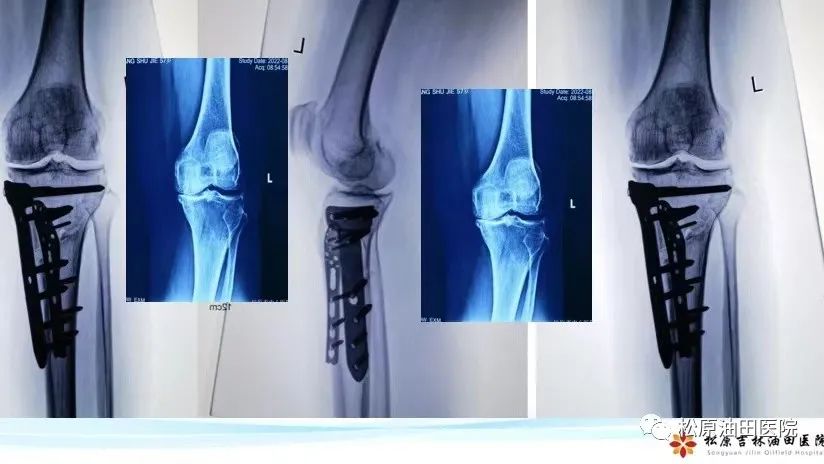

据悉,今年松原吉林油田医院放射线科引进开展负重位下肢全长的影像系统检查项目,它可以全面观察骨与关节的形态、密度的改变,负重位真实对生理角度、畸形角度、力线进行测量,为下肢畸形矫正、植骨术,尤其是膝关节矫形术或关节置换术前、术后提供了有力的测量依据。在此基础上,医院骨三科主任冯宪发团队在松原率先开展了不换膝关节“微创保膝”治疗新技术,此技术为国内领先技术,达到了推迟或不换膝关节治疗膝关节骨性关节炎。

到目前,松原市内外已有11位患者享得了新技术带来的福利,深得患者的好评。